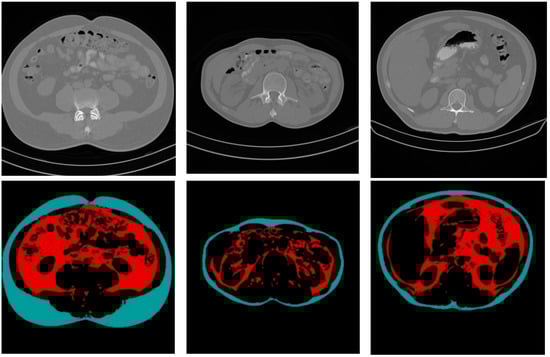

Figure 10 shows some CT sample images and the results of fat segmentation and classification. The top row images are the original DICOM images, and the bottom row presents the results of fat segmentation and classification for the top DICOM images. The red color region represents the VF tissue, and the turquoise color region represents the SF tissues.

Figure 10. Samples of the original CT images and the results of fat segmentation and classification.